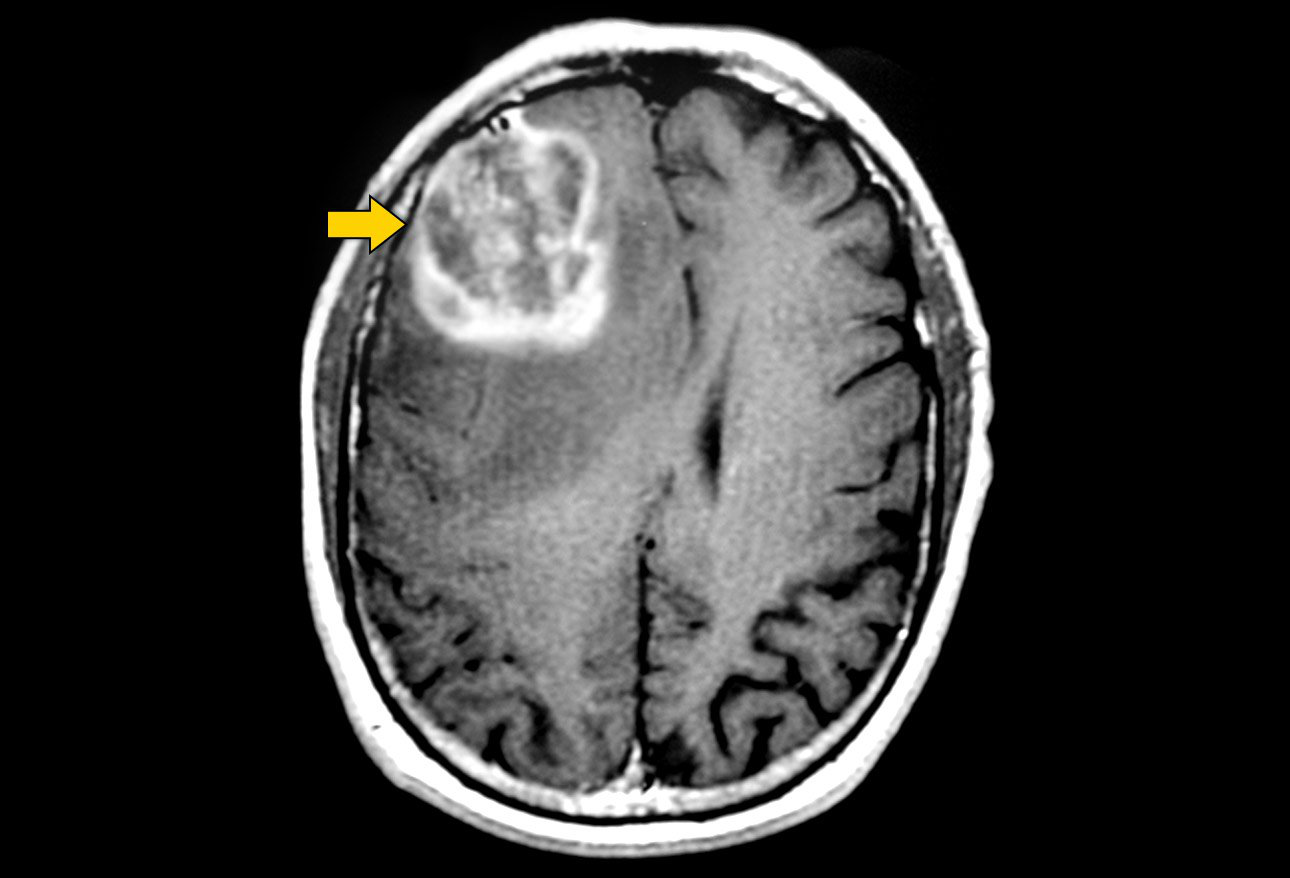

什么是脑瘤? 脑组织、脑神经末梢、脑膜、颅骨、颅骨或颅骨肌肉的肿瘤称为原发性脑瘤,而从身体其他器官(肺、乳腺、腺等)延伸的肿瘤称为转移瘤或继发...

恶性脑瘤 是一种快速增长的癌症,它会扩散到大脑和脊柱的其他部位。一般来说,根据脑瘤的恶性程度,例如肿瘤生长的速度和治疗后复发的可能性,脑瘤...

脑膜瘤 是发生在脑膜上的脑瘤,脑膜是包围和保护大脑和脊髓的组织(图1)。尽管大多数脑膜瘤不是癌性的,但当它们生长并压迫大脑或脊髓的重要部位时,...

开颅手术切除内源性 脑肿瘤 的目的是建立组织诊断,好转神经症状,。在低级别 星形细胞瘤 、恶性胶质瘤和单一脑转移的患者中,细胞减少手术与生存率...